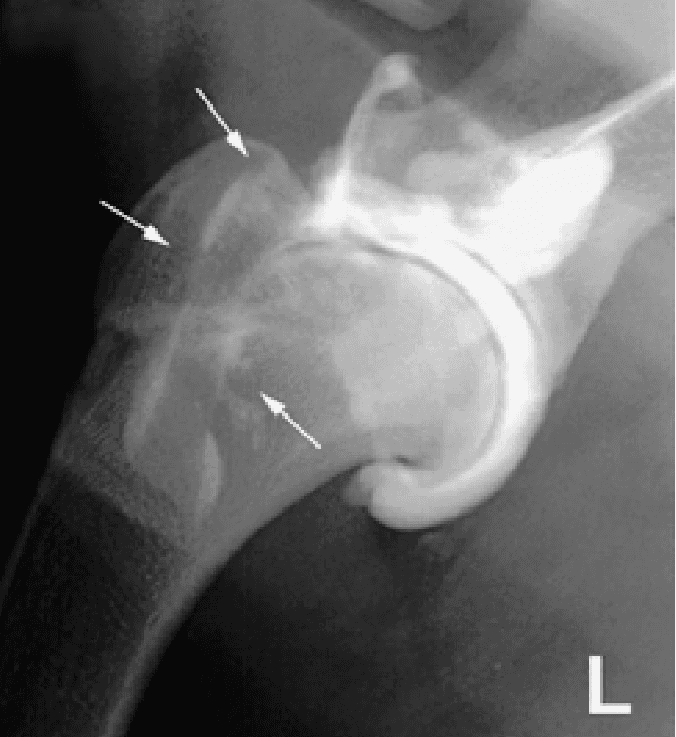

The disease is suspected when pain is elicited on flexion of the shoulder with physical examination. An x-ray of the shoulder is usually enough to confirm the diagnosis. In some cases, a CT scan may be recommended to identify small lesions not clearly visible on x-rays.

Both shoulders should be evaluated because OCD will commonly affect both limbs.